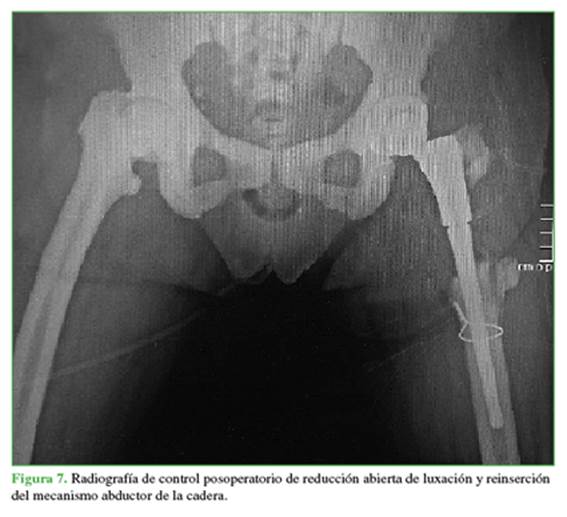

En marzo de 2018, sin antecedente de caída, la paciente consulta por el servicio de urgencias de la institución por dolor intenso en cadera izquierda, acortamiento de la extremidad y limitación para el apoyo y la marcha. La radiografía de control evidencia luxación posterior de prótesis total de cadera izquierda (Figura 6). Tras varios intentos de reducción cerrada de la luxación bajo anestesia general y persistencia de inestabilidad, se realiza reducción abierta de luxación de prótesis, con hallazgo intraoperatorio de desinserción de mecanismo abductor de la cadera, sin signos de infección o aflojamiento de los componentes, por lo que se realiza reparación y nueva fijación a aleta de metáfisis de vástago femoral, sin complicaciones (Figura 7).